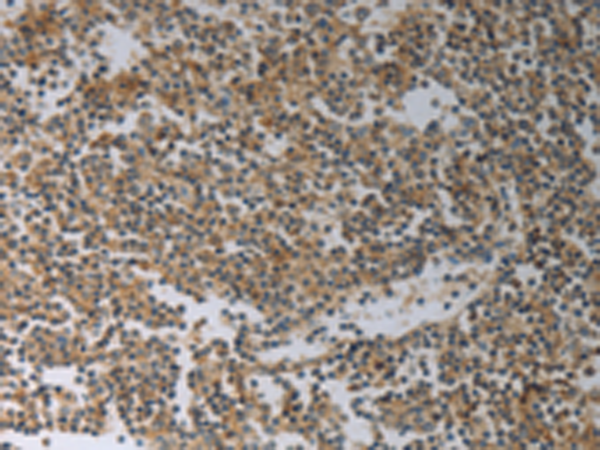

分类: 科研抗体货号: P04205别名: JAB, CIS1, SSI1, TIP3, CISH1, SSI-1, SOCS-1应用: WB,IHC反应种属: Human, Mouse, Rat